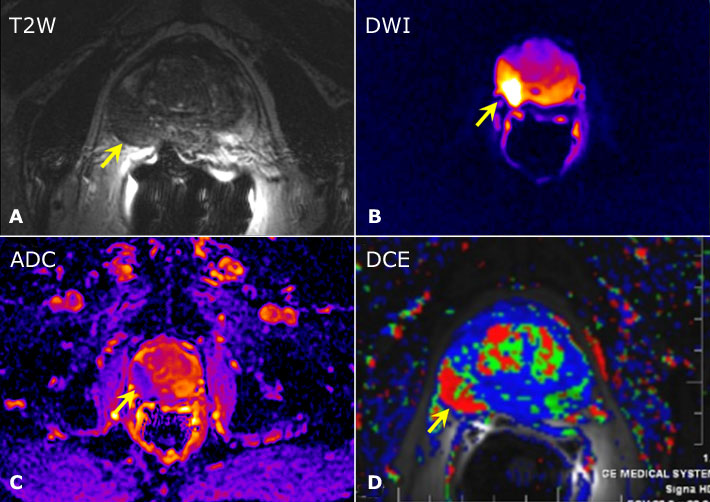

Utilidad de la resonancia magnética multi-paramétrica en la evaluación del PSA elevado

24 enero 2017

Los hallazgos de este estudio de imágenes permitirían reducir en un 25% las biopsias prostáticas sin perder sensibilidad para el cáncer de próstata clínicamente significativo. Lancet, 17 de enero de 2017